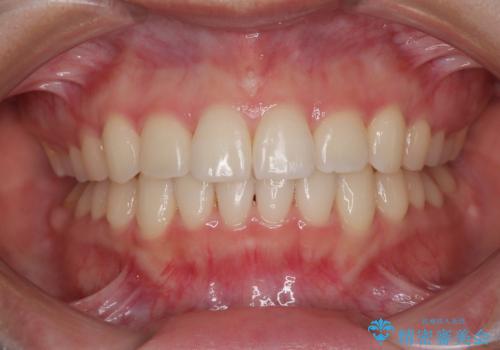

舌の突出癖により、出っ歯仕上がりとなる可能性がありましたが、舌のトレーニングを頑張っていただき、1年強で終えることができました。